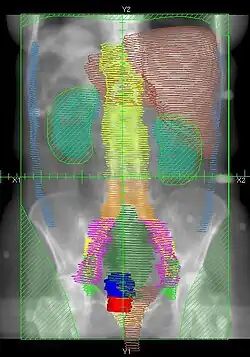

RT Technique

- There are multiple techniques, but typically Whole Abdomen RT is given to 22.5-25 Gy, followed by boost to PA LNs and whole pelvis to 45-50.4 Gy

- Dose: 22.5-25Gy in 130-150cGy/fx.

- Simulation: Supine with Alpha cradle.

- Fields: AP/PA single fields or 4-field technique

- Blocks:

- Kidneys – 50% transmission block or block after 15Gy.

- Liver – Block at 25Gy. Block not used by some institutions.

![]() |

Example of a PA whole abdomen/pelvis radiation therapy treatment field used at Tufts/Brown residency program. Actual patient contours should guide field design.